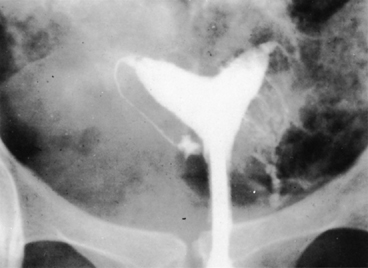

No characteristic radiographic features are pathognomonic for genital tract TB, although certain findings should raise suspicion of its possibility. Barter and associates reported that an abdominal film may show calcified pelvic and abdominal lymph nodes, a characteristic and recognized sequela of healed genital tract TBs.83 Hysterosalpingography may reveal certain abnormalities that suggest the possibility of pelvic TB. The uterine cavity is classically shriveled and deformed, with associated intrauterine adhesions and lymphatic extravasation (Fig. 6). The fallopian tubes often show ragged outlines with multiple strictures, giving a beaded appearance (Fig. 7); in some patients, the entire tube appears rigid and may exhibit small terminal sacculations of the ampullary end (Fig. 8). Fistulous tracts between the genital tract and other pelvic organs may be identified. Occlusion of the digital end of the fallopian tubes is common, although marked hydrosalpinx is usually uncommon (Fig. 9), Calcification of the organs may be visualized.84,85 If a water-soluble contrast medium is used and the usual precautions are observed, complications can be minimized. Hysterosalpingography is contraindicated in the presence of recent acute pelvic infection, and many reports described exacerbation of pelvic TB following the procedure.86

Fig. 6. Radiograph demonstrates lymphatic extravasation, a deformed uterine cavity, and a narrow-rigid fallopian tube with a dilated and closed fimbrial end on the right side.